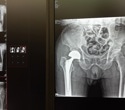

Total hip arthroplasty (hip replacement) is a common treatment for hip osteoarthritis, a degenerative joint disease caused by cartilage in the hip joint wearing down. However, clinical outcomes vary between patients, and the best timing for surgery remains unclear.

Osteoarthritis, which is the most common form of arthritis, is a growing issue that affects more than 500 million people worldwide. It often causes severe pain and joint stiffness and significantly impacts quality of life. For hip osteoarthritis, total hip arthroplasty, where surgeons replace the damaged joint with an artificial one, is an effective but last-resort treatment. However, determining the right time for surgery remains difficult. Doctors typically rely on factors such as pain intensity or the severity of osteoarthritis as assessed by hip X-rays, but research has been inconclusive about whether these criteria reliably predict good postoperative outcomes.